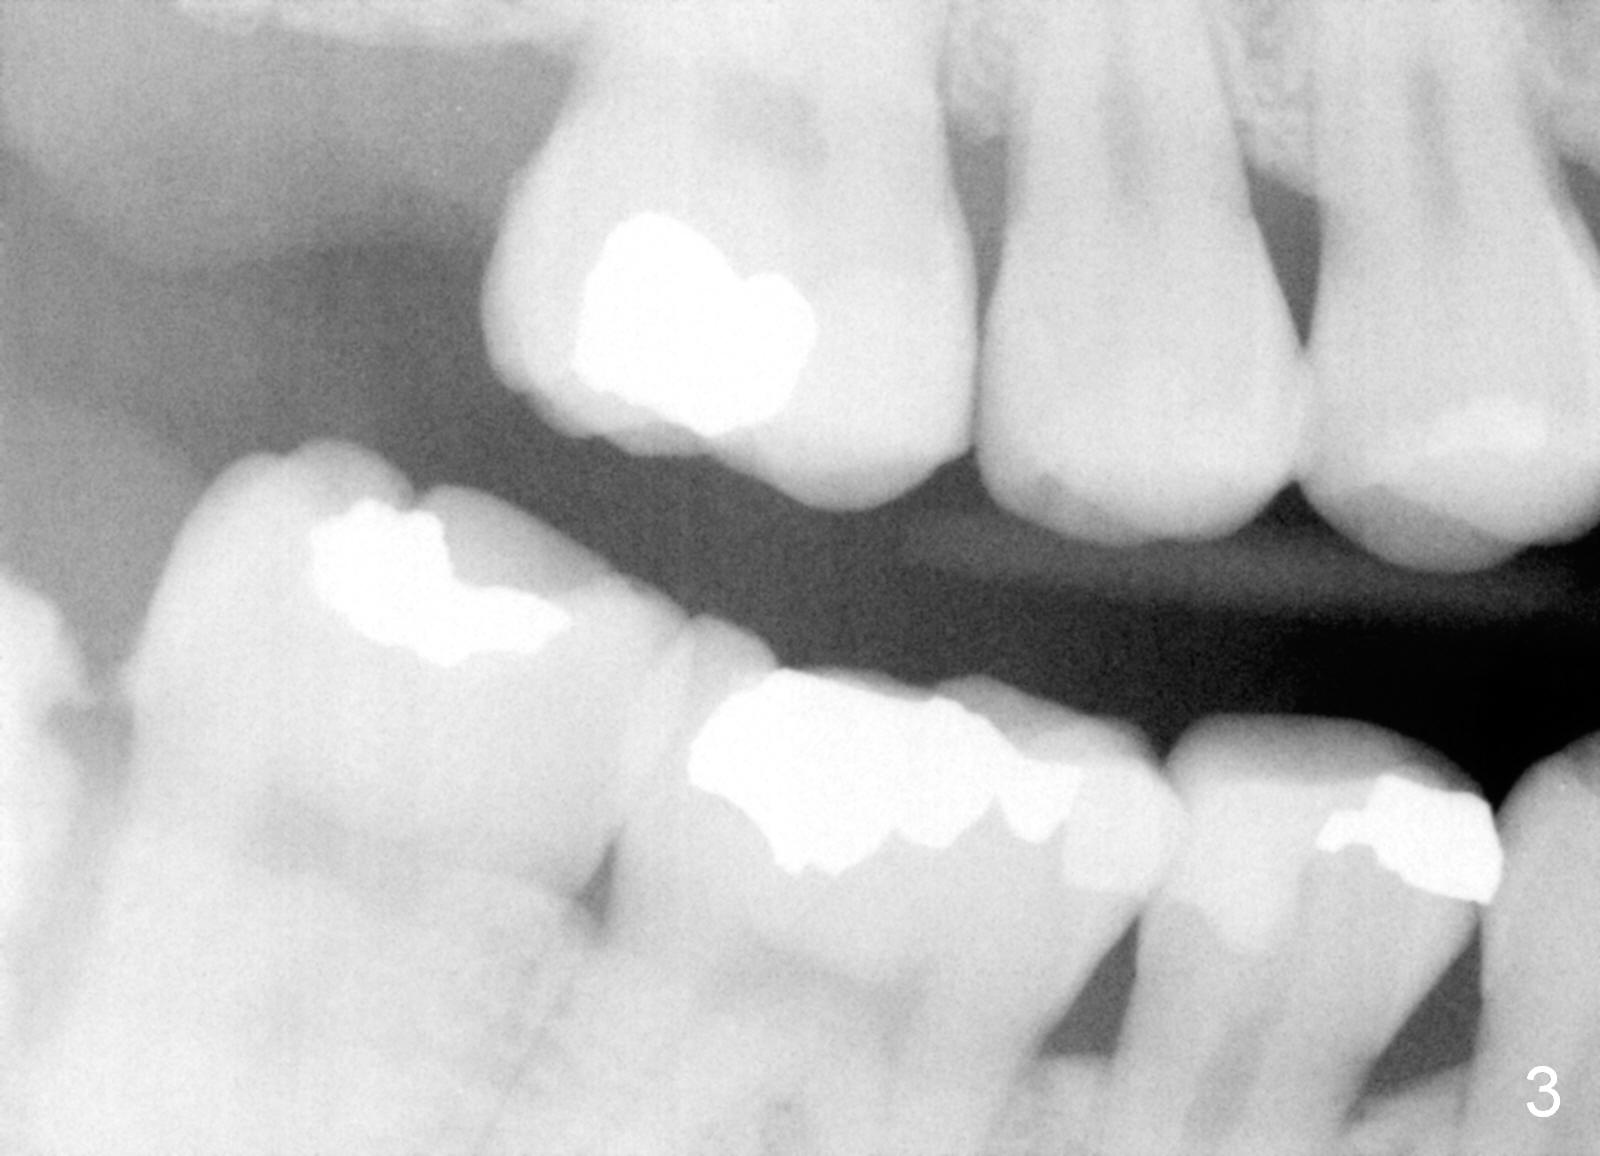

The panoramic X-ray (Fig.1) was taken on 12/12/2011 when the teeth #15 and 16 were extracted. The teeth #1 and 2 were removed half a year later. Bitewings (Fig.2-5), PAs (Fig.6,7) and upper occlusal mirror photo were taken on 02/11/2015. Pay attention to Fig.2.